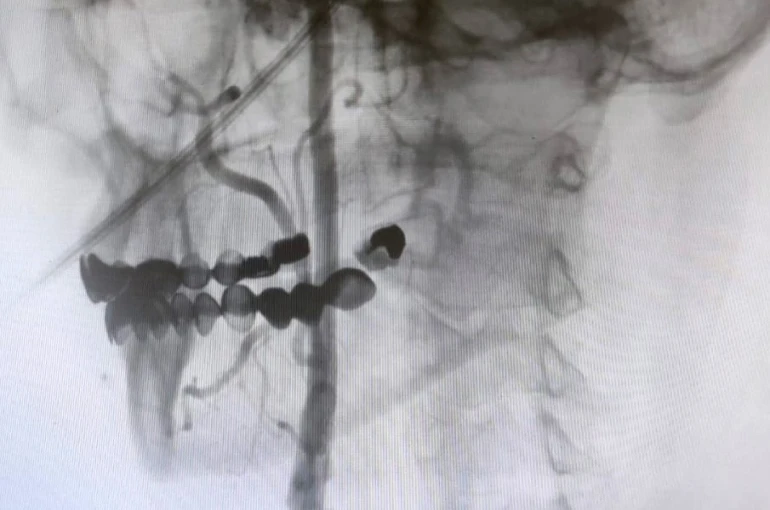

"Boyun damarlarını açma işlemi iki şekilde yapılabilir. Bir karotis endarterektomi dediğimiz ameliyatla bir diğer yöntem ise perkutan girişim dediğimiz stent yöntemiyle açılabilir. Biz kliniğimizde nöroloji ve kardiyoloji olarak bir konsey yapıyoruz. Damarı ciddi tıkalı olan ve buna bağlı felç geçirmiş hastalarda bu konseyde hastaya işlem yapıp yapmama kararı veriyoruz. Verdiğimiz karar çerçevesinde eğer hastaya işlem kararı vermişsek femoral arter dediğimiz kasık arterinden bir şitle 6 ya da 7 F çapında bir şitle ince bir boruyla bu damara giriş yapıyoruz ve boyun damarlarına ulaşıyoruz. Özellikle teller, filtreler ve stentlerle bu damarları açıp hastanın tedavisini gerçekleştiriyoruz. İşlem ameliyatsız olduğu için hastamız ertesi gün rahat bir şekilde problem olmazsa işlemde taburcu olabiliyor bu işlemden sonra. Bu işlemin yapılması için özellikle anjiografinin olduğu girişimsel nöroloji uzmanının ve girişimsel kardiyoloji uzmanının olduğu ve bu konuda yeterli vaka tecrübesine ve deneyime sahip uzmanların olduğu merkezler gerekir. Bunu yapabilmek için belli bir vaka sayısına ulaşmak ve bu konuda tecrübeli olmak gerekiyor. Biz de Manisa Şehir Hastanesi’ndeki girişimsel kardiyoloji ve nöroloji uzmanları olarak bu işlemi kliniğimizde efektif bir şekilde gerçekleştiriyoruz."